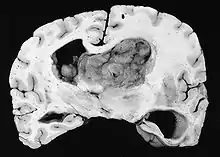

| GFAP stained microscopic section of a subependymal giant cell astrocytoma | |

Subependymal giant cell astrocytoma (SEGA, SGCA, or SGCT) is a low-grade astrocytic brain tumor (astrocytoma) that arises within the ventricles of the brain.[1] It is most commonly associated with tuberous sclerosis complex (TSC). Although it is a low-grade tumor, its location can potentially obstruct the ventricles and lead to hydrocephalus.